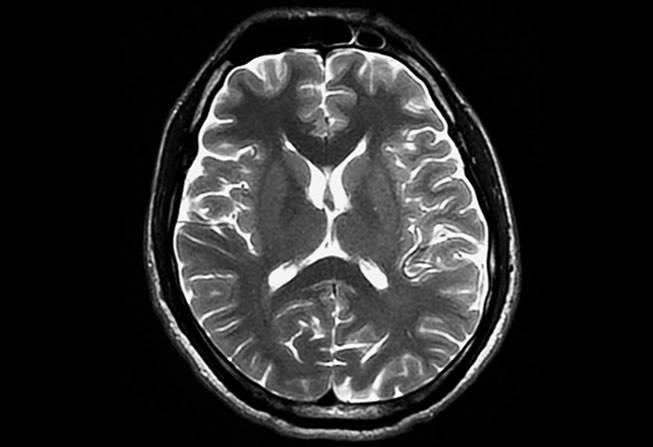

resonancia magnética

estudios